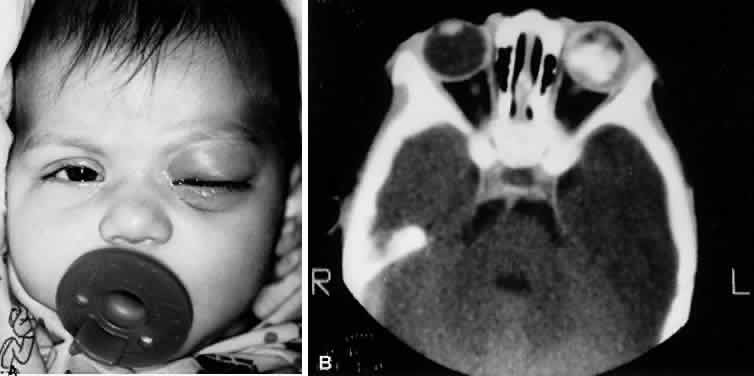

H. influenzae type B cellulitis typically begins with mild upper respiratory tract infection, fever, leukocytosis, and unilateral hyperemia and edema of the soft tissues of the eyelids. A sharply demarcated, purple discoloration of the skin of the eyelids and adnexal region is characteristic (Fig. 12). Mild conjunctival hyperemia and chemosis may be present.

Fig. 12. A. Two-year-old African-American girl with preseptal cellulitis due to type b H. influenzae. B. Seven-year-old white boy with preseptal cellulitis due to S. pneumoniae.

Preseptal cellulitis secondary to infection of the subcutaneous tissue of the cheek and face is a rare condition affecting infants up to 9 months old (Fig. 19).41 The infection begins in the gums and superior alveolar tooth buds, apparently following contact with mastitis or with other contaminated sources. The organism responsible is almost exclusively Staphylococcus aureus. The infectious process spreads in the subcutaneous tissue of the face to reach the preseptal area. Secondary infection of the maxilla and rudimentary maxillary sinus may occur. Facial and preseptal cellulitis can also occur from untreated dental caries in young children and older persons when there is bacterial invasion of the dental pulp progressing to involvement of the alveolar ridge.42

Fig. 19. Cellulitis of the face in a 2-week-old infant.